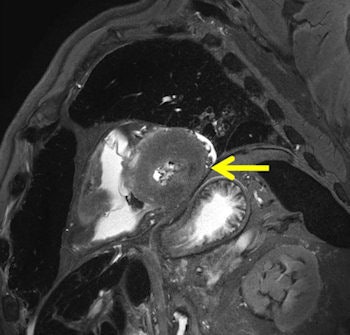

"From the MR point of view, a gunshot to the head is less interesting. With MRI, the gunshot channel is comparably seen as in autopsy, but for pedestrians killed by cars, MR sometimes detects more lesions than autopsy and in sudden cardiac deaths even more than histology can," he said.

Sudden cardiac death happens mainly due to ventricular tachycardia with no direct findings in the heart in autopsy or histology as speed of death leaves insufficient time for recognizable myocardial changes. Jackowski's most recently published study demonstrates that unenhanced MR can show peracute myocardial infarctions even in the absence of a myocardial autopsy finding, and when histology may fail to show ischemic alterations.